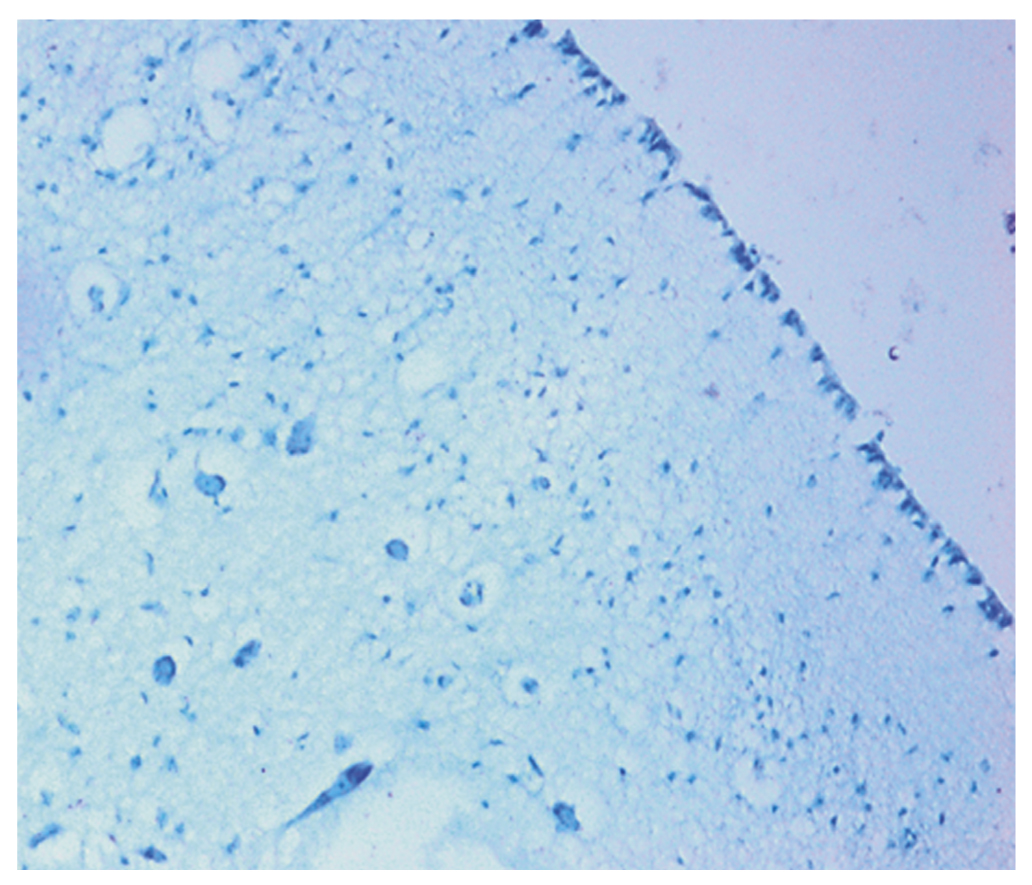

Вскрытия детей проводили в соответствии с медицинскими технологиями, применяемыми при производстве судебно-медицинских экспертиз [8]. Детальному макроскопическому изучению был подвергнут ствол мозга с учетом особенностей анатомического строения продолговатого мозга и локализации ядер черепно-мозговых нервов в дне ромбовидной ямки (рис. 1–4). При гистологическом исследовании кусочки внутренних органов и головного мозга подвергали стандартной парафиновой обработке, окрашивали гематоксилин-эозином и пикрофуксином по Ван Гизону в 100% случаев. Кусочки стволовых отделов мозга были дополнительно окрашены гистохимическими методами: по Вейгерту — на эластические волокна, по Шпильмейеру — на миелиновые волокна, толуидиновым синим по Нисслю — для изучения структуры нервной ткани. Общий объем изученных гистологических препаратов составил 12 321 срезов, которые изучали при помощи светового микроскопа «Olympus-CX 31» с микрофотографированием. Микроморфометрия производилась с использованием программного обеспечения Image J2x, что позволило определить площадь объекта, выделенного на фотографии гистологического препарата. При изучении микроскопических срезов продолговатого мозга в основной группе (СВСД) и группе контроля провели статистический анализ морфометрических измерений с помощью пакета статистических и прикладных программ Statistica 6.0 (США).

Рис. 4. Заднее ядро блуждающего нерва продолговатого мозга с хроматолизом в нейронах и нейронофагией (мальчик, 3 месяца 12 дней). Окраска толуидиновым синим по Нисслю. Ув. 100

Детальному исследованию и анализу был подвергнут ствол мозга с учетом особенностей анатомического строения продолговатого мозга и локализации ядер черепно-мозговых нервов в дне ромбовидной ямки (см. рис. 3 и 4). В 54 случаях (72,9%) при гистохимической окраске срезов толуидиновым синим по Нисслю в заднем (вегетативном) ядре блуждающего нерва, расположенном в проекции вагусного треугольника ромбовидной ямки, обнаружены явления хроматолиза, кариолизиса и нейронофагии [11]. Морфометрические показатели в нейронах и сосудах ствола мозга были статистически значимы между показаниями контрольной и опытной группы в сопоставимых возрастах (р ≤ 0,01).